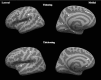

Magnetic resonance imaging data were acquired at ∼24 h and ∼3 months post-injury on mild traumatic brain injury (mTBI; n = 75) and orthopedic injury (n = 60) cohorts. The mTBI subjects were randomly assigned to a treatment group with atorvastatin or a non-treatment mTBI group. The treatment group was further divided into drug and placebo subgroups. FreeSurfer software package was used to compute cortical thickness based on the three dimensional T1-weighted images at both time-points. Cross-sectional analysis was carried out to compare cortical thickness between the mTBI and control groups. Longitudinal unbiased templates were generated for all subjects and cortical thickness measurements were compared between baseline and follow-up scans in the mTBI group. At baseline, significant reduction in cortical thickness was observed in the left middle temporal and the right superior parietal regions in the mTBI group, relative to the control group (p = 0.01). At follow-up, significant cortical thinning was again observed in the left middle temporal cortex in the mTBI group. Further analysis revealed significant cortical thinning only in the non-treatment group relative to the control group. In the follow-up, small regions with significant but subtle cortical thinning and thickening were seen in the frontal, temporal, and parietal lobes in the left hemisphere in the non-treatment group only. Our results indicate that cortical thickness could serve as a useful measure in identifying subtle changes in mTBI patients.